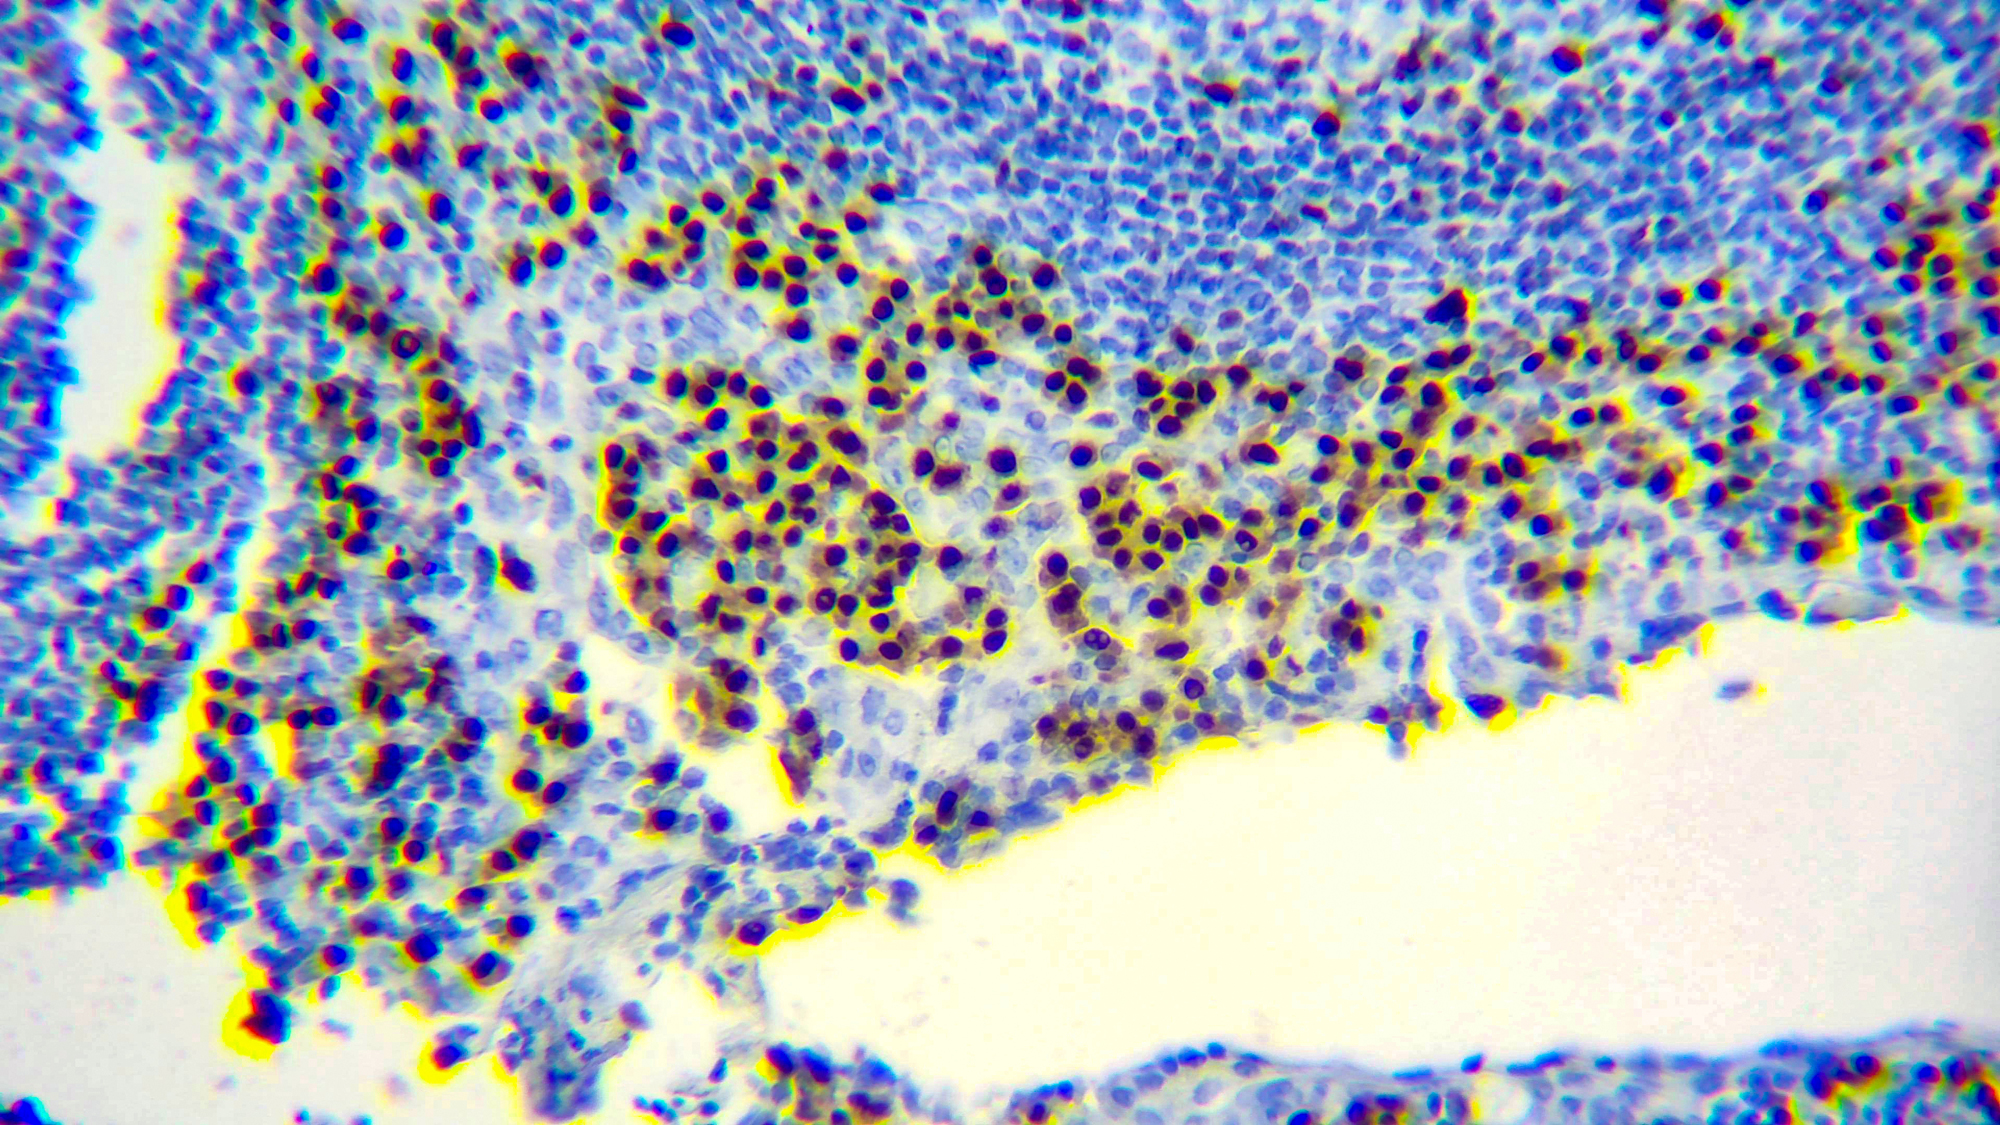

Multiple myeloma oncogene-1 (MUM1) is a 50kDa protein encoded by the MUM1 gene. This antibody stains MUM1 protein, which is expressed in a subset of B cells in the light zone of the germinal center, plasma cells, activated T cells and a wide spectrum of related hematolymphoid neoplasms. This antibody is useful in the sub classification of lymphoid malignancies.

| Positive Control Tissue | Tonsil |